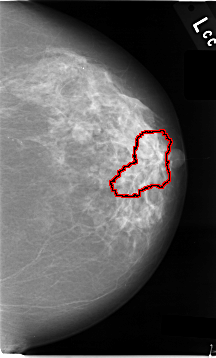

C_0006_1.LEFT_MLO

FILE: C_0006_1.LEFT_MLO.OVERLAY

TOTAL_ABNORMALITIES 1

ABNORMALITY 1

LESION_TYPE MASS SHAPE ARCHITECTURAL_DISTORTION MARGINS N/A

ASSESSMENT 4

SUBTLETY 1

PATHOLOGY MALIGNANT

TOTAL_OUTLINES 1

BOUNDARY